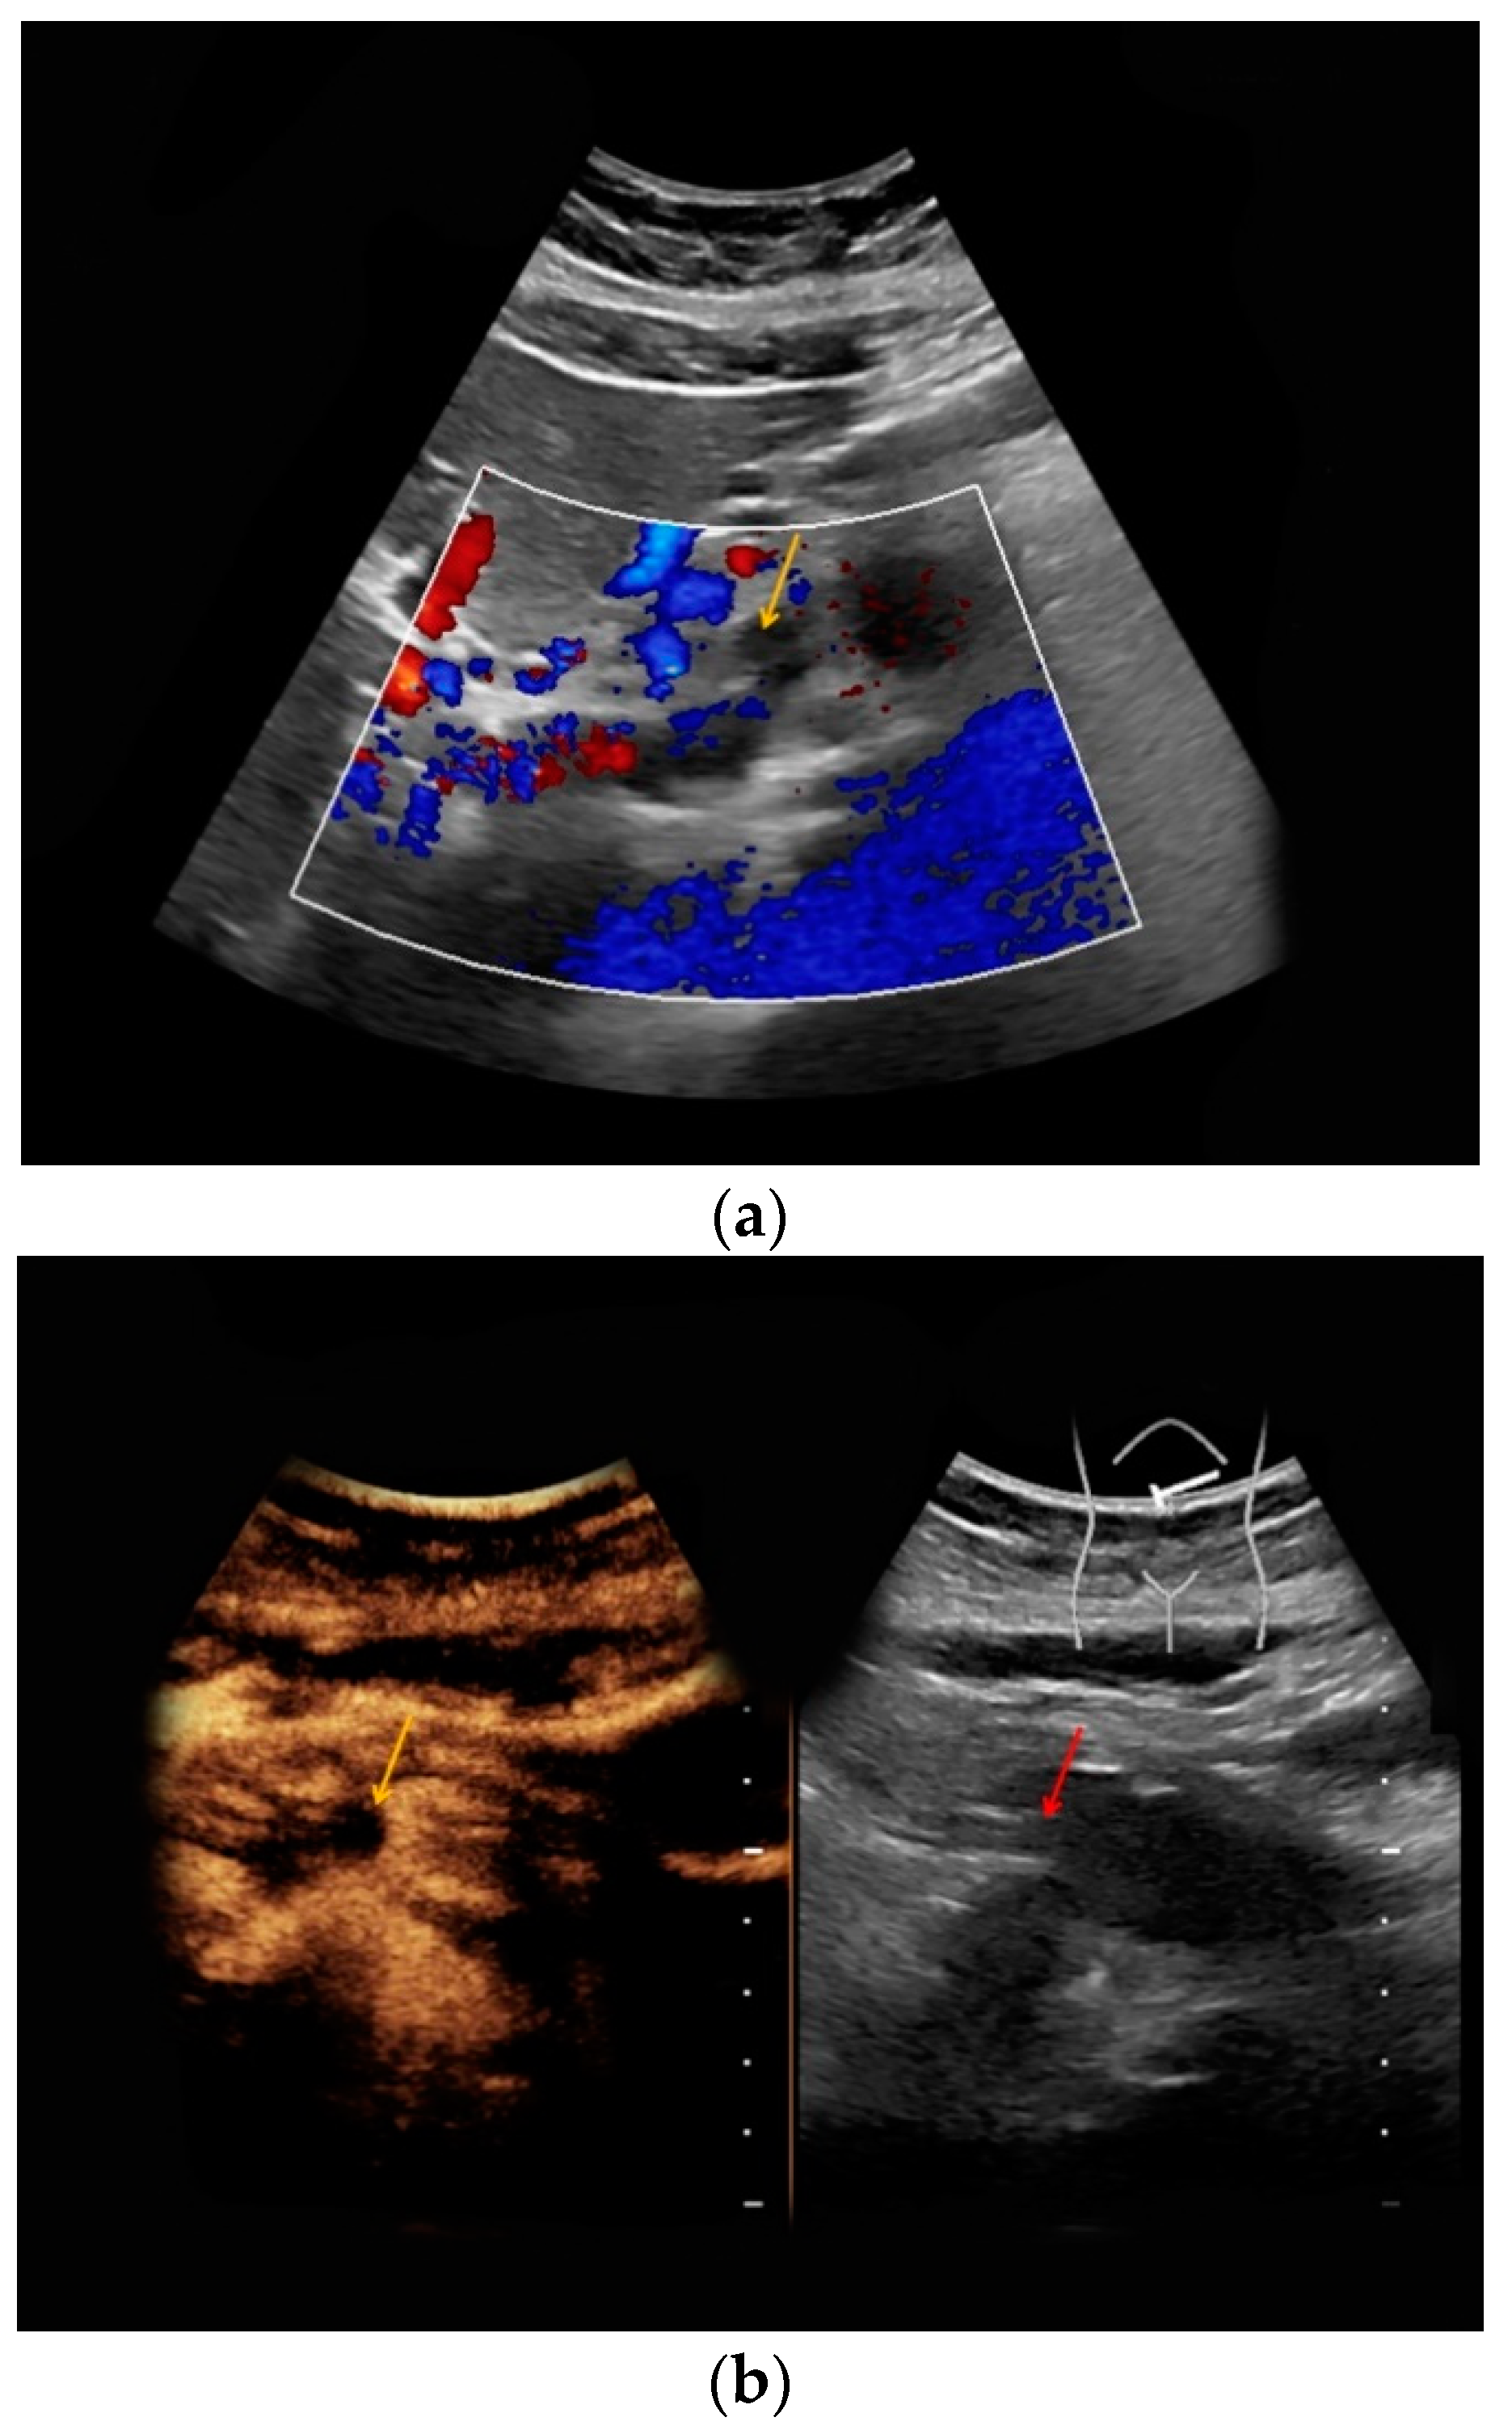

| #4 | 33 | 17 | Gallbladder polyp | B-mode: hyperechoic, 0.6 cm Doppler: no hypervascularization CEUS: homogeneous, late contrast enhancement | - |